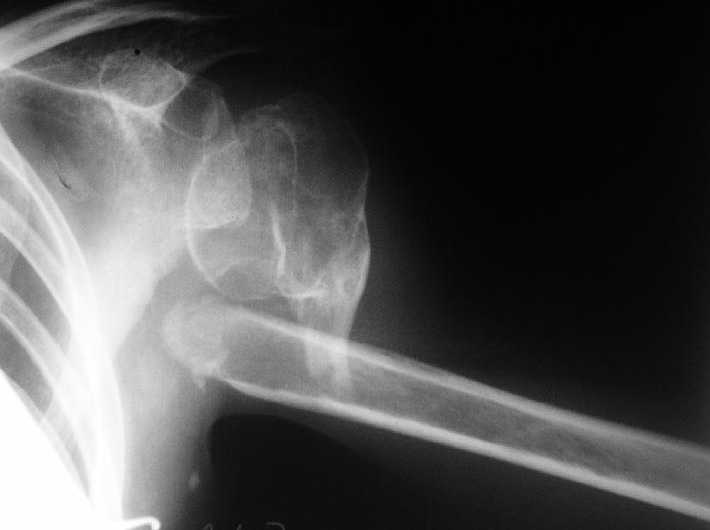

Несращение плеча, деформация головки

Здравствуйте уважаемые коллеги.Помогите, пожалуйста, определиться с тактикой.Больная 40 лет, множественная травма в июне 2007 года. Лечилась в городской больнице.

Повреждение проксимального отдела плеча вели консервативно в гипсовой повязке. В настоящее время больную беспокоят боли в области плечевого сустава, слабость верхней конечности. Амплитуда движений в плечевом суставе в пределах 30-40 градусов. Пациентка хотела бы увеличить объем движений и силу.Движения сейчас в основном за счет ложногго сустава. Варанты - остеосинтез, артролиз, эндопротезирование, оставить как есть. Как-то н один однозначно не привлекает.

Андрей! На мой взгляд 40 лет и жить с "такой" рукой помоему не очень хочеться. Я бы сделал КТ с целью оценить жизнеспособность головки плечевой кости. И выбор по ситуации: при выраженом асептическом некрозе-ревизионное эндопротезирование, при жизнеспособной-резекция

ложного сустава, декортикация и фиксация блокируемой пластиной-ранняя разработка амплитуды движний в плечевом суставе. Думаю что не все